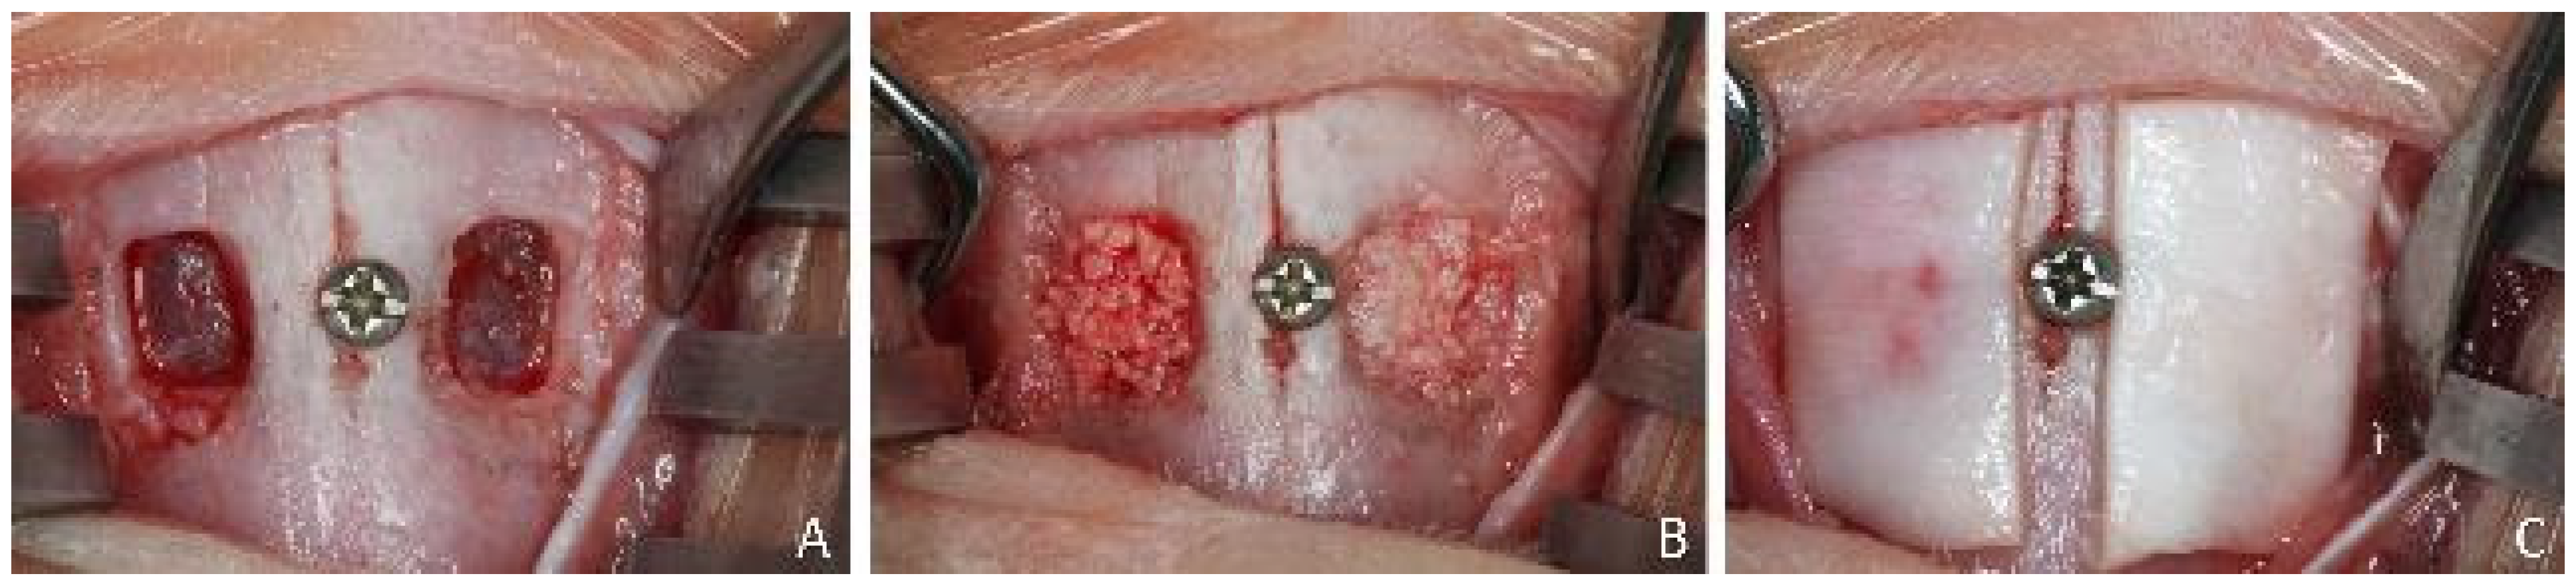

2.5. MicroCT Evaluations

2.7. Calibration for Histomorphometric Evaluations

2.8. Histomorphometric Evaluations